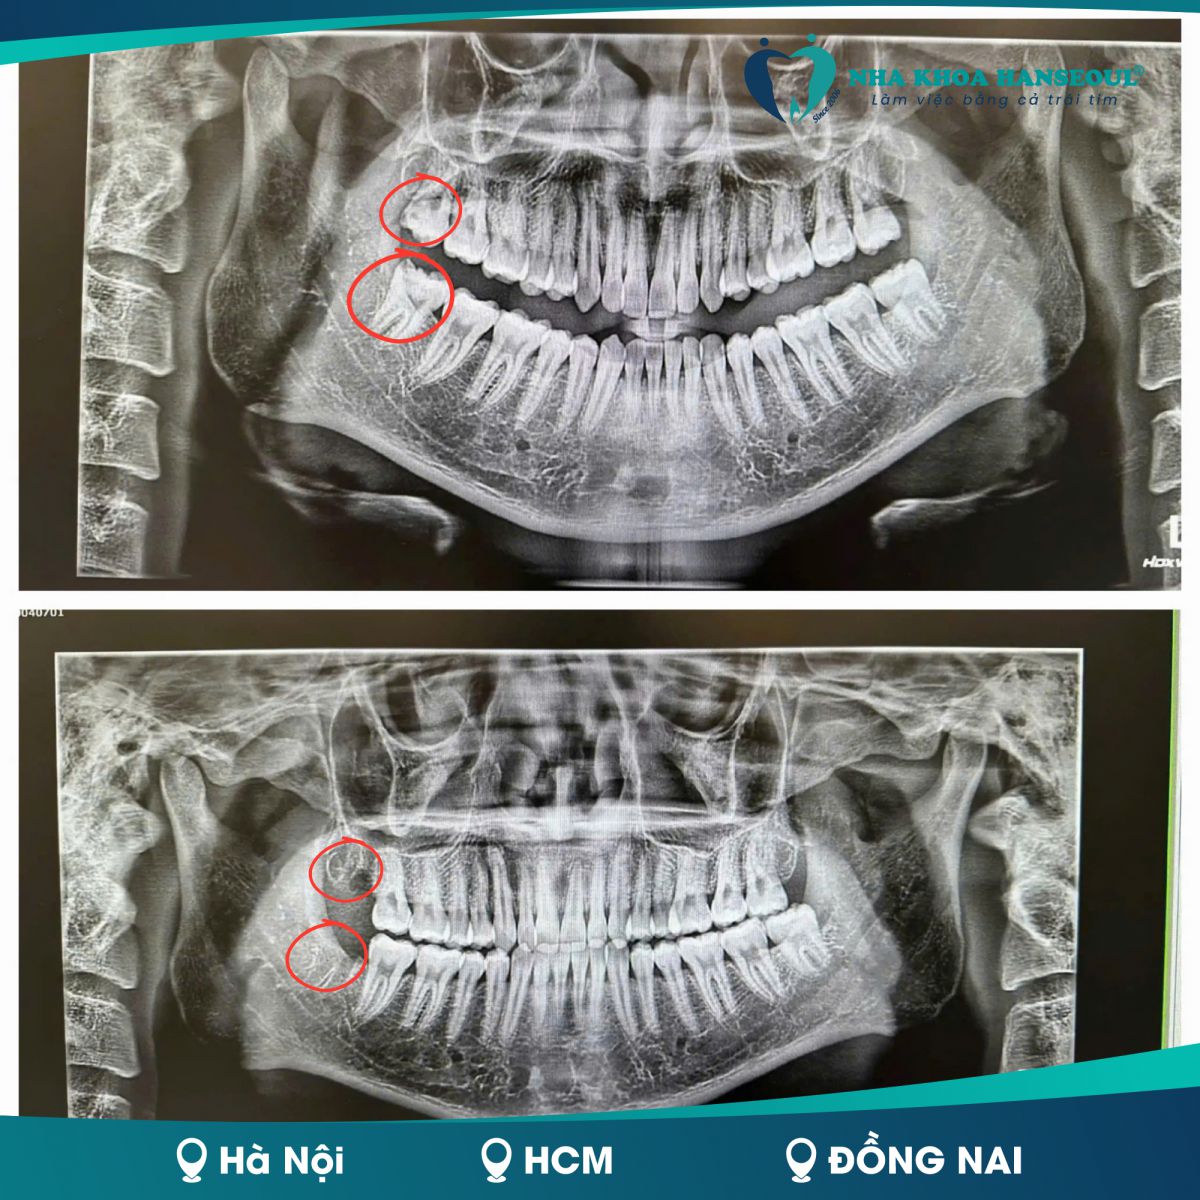

Anh Thắng đã quyết định “xử lý” cùng lúc 2 răng khôn (R18 hàm trên và R48 hàm dưới) với tâm lý không khỏi lo lắng. Trước đó, anh nghe nhiều người chia sẻ về những trải nghiệm đau đớn sau khi nhổ răng khôn khiến anh khá ái ngại.